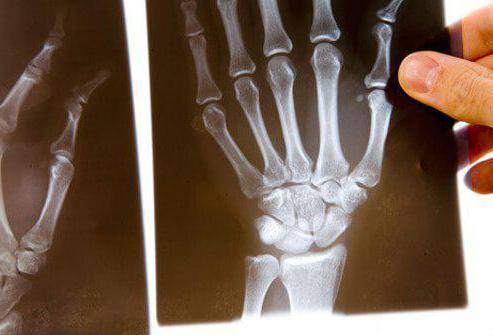

Третья стадия

Третья степень артрита характеризуется развитием типичной клинической и рентгенологической картины. Все относящиеся к первым двум степеням артроза изменения наблюдаются и на третьей, но с гораздо большей выраженностью.

Патологические изменения при артрите суставов пальцев рук

- Прогрессирование остеопороза с увеличением в размерах суставной щели.

- Появление огромного количества эрозий на хрящевой поверхности.

- Заметны множественные подвывихи пораженных суставов (рентгенография лучше всего фиксирует их на мелких хрящах).